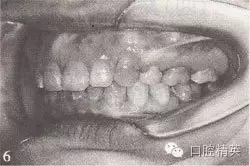

參見圖9-33 雙側(cè)后牙鎖頜矯治前后

A.雙側(cè)后牙鎖頜矯治前

B.雙側(cè)后牙鎖頜矯治后